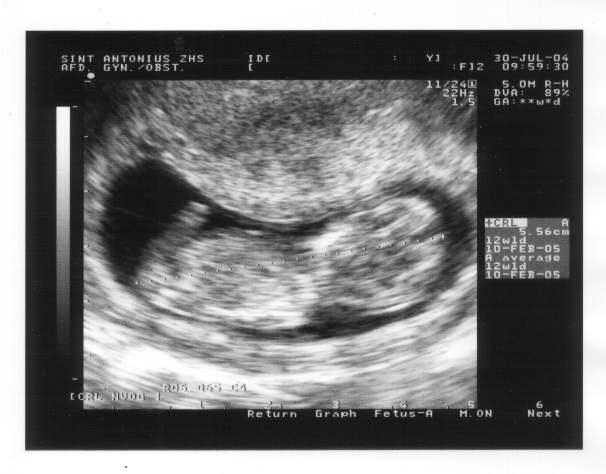

30 juli 2004

Voor de mensen die nog meer willen weten: een groeitabel